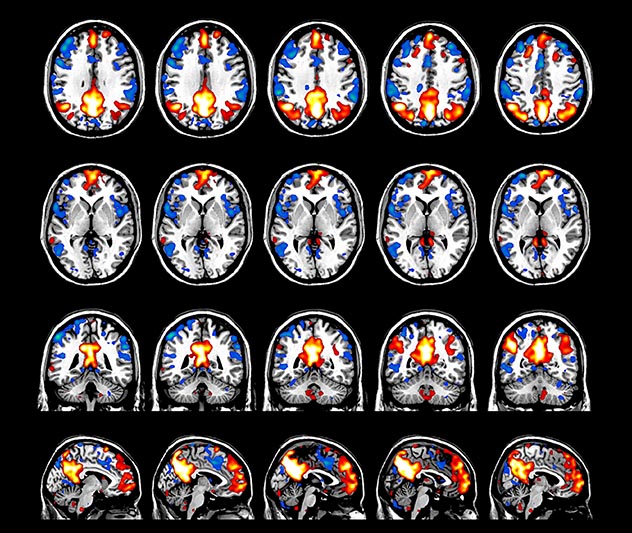

MultiBand SENSE, fMRI matching facial expressions

fMRI of viewing and matching facial expressions

BOLD fMRI activation, depicted in color, of left anterior insula (MNI plane z = 8 mm) in a single subject by a contrast between viewing and matching faces with negative emotion (angry, sad, scared) versus happy faces. The voxelwise threshold is p < 0.001, and colored voxels survive false discovery rate correction to p < 0.05. The activated voxels in color are overlaid on the subject's own 3D-TFE image displayed in grayscale, after transforming the data to MNI space. The fMRI pulse sequence was a single shot FFE echo planar acquisition using MultiBand SENSE factor 6, dS SENSE factor 1, isotropic voxel size 2.4 mm, 60 transverse slices, TR 950 ms, TE 30 ms, flip angle 52 degrees, 517 dynamic scans, total scan duration 8:21 minutes. Image provided by James M. Bjork, PhD, Associate Professor of Psychiatry at VCU.